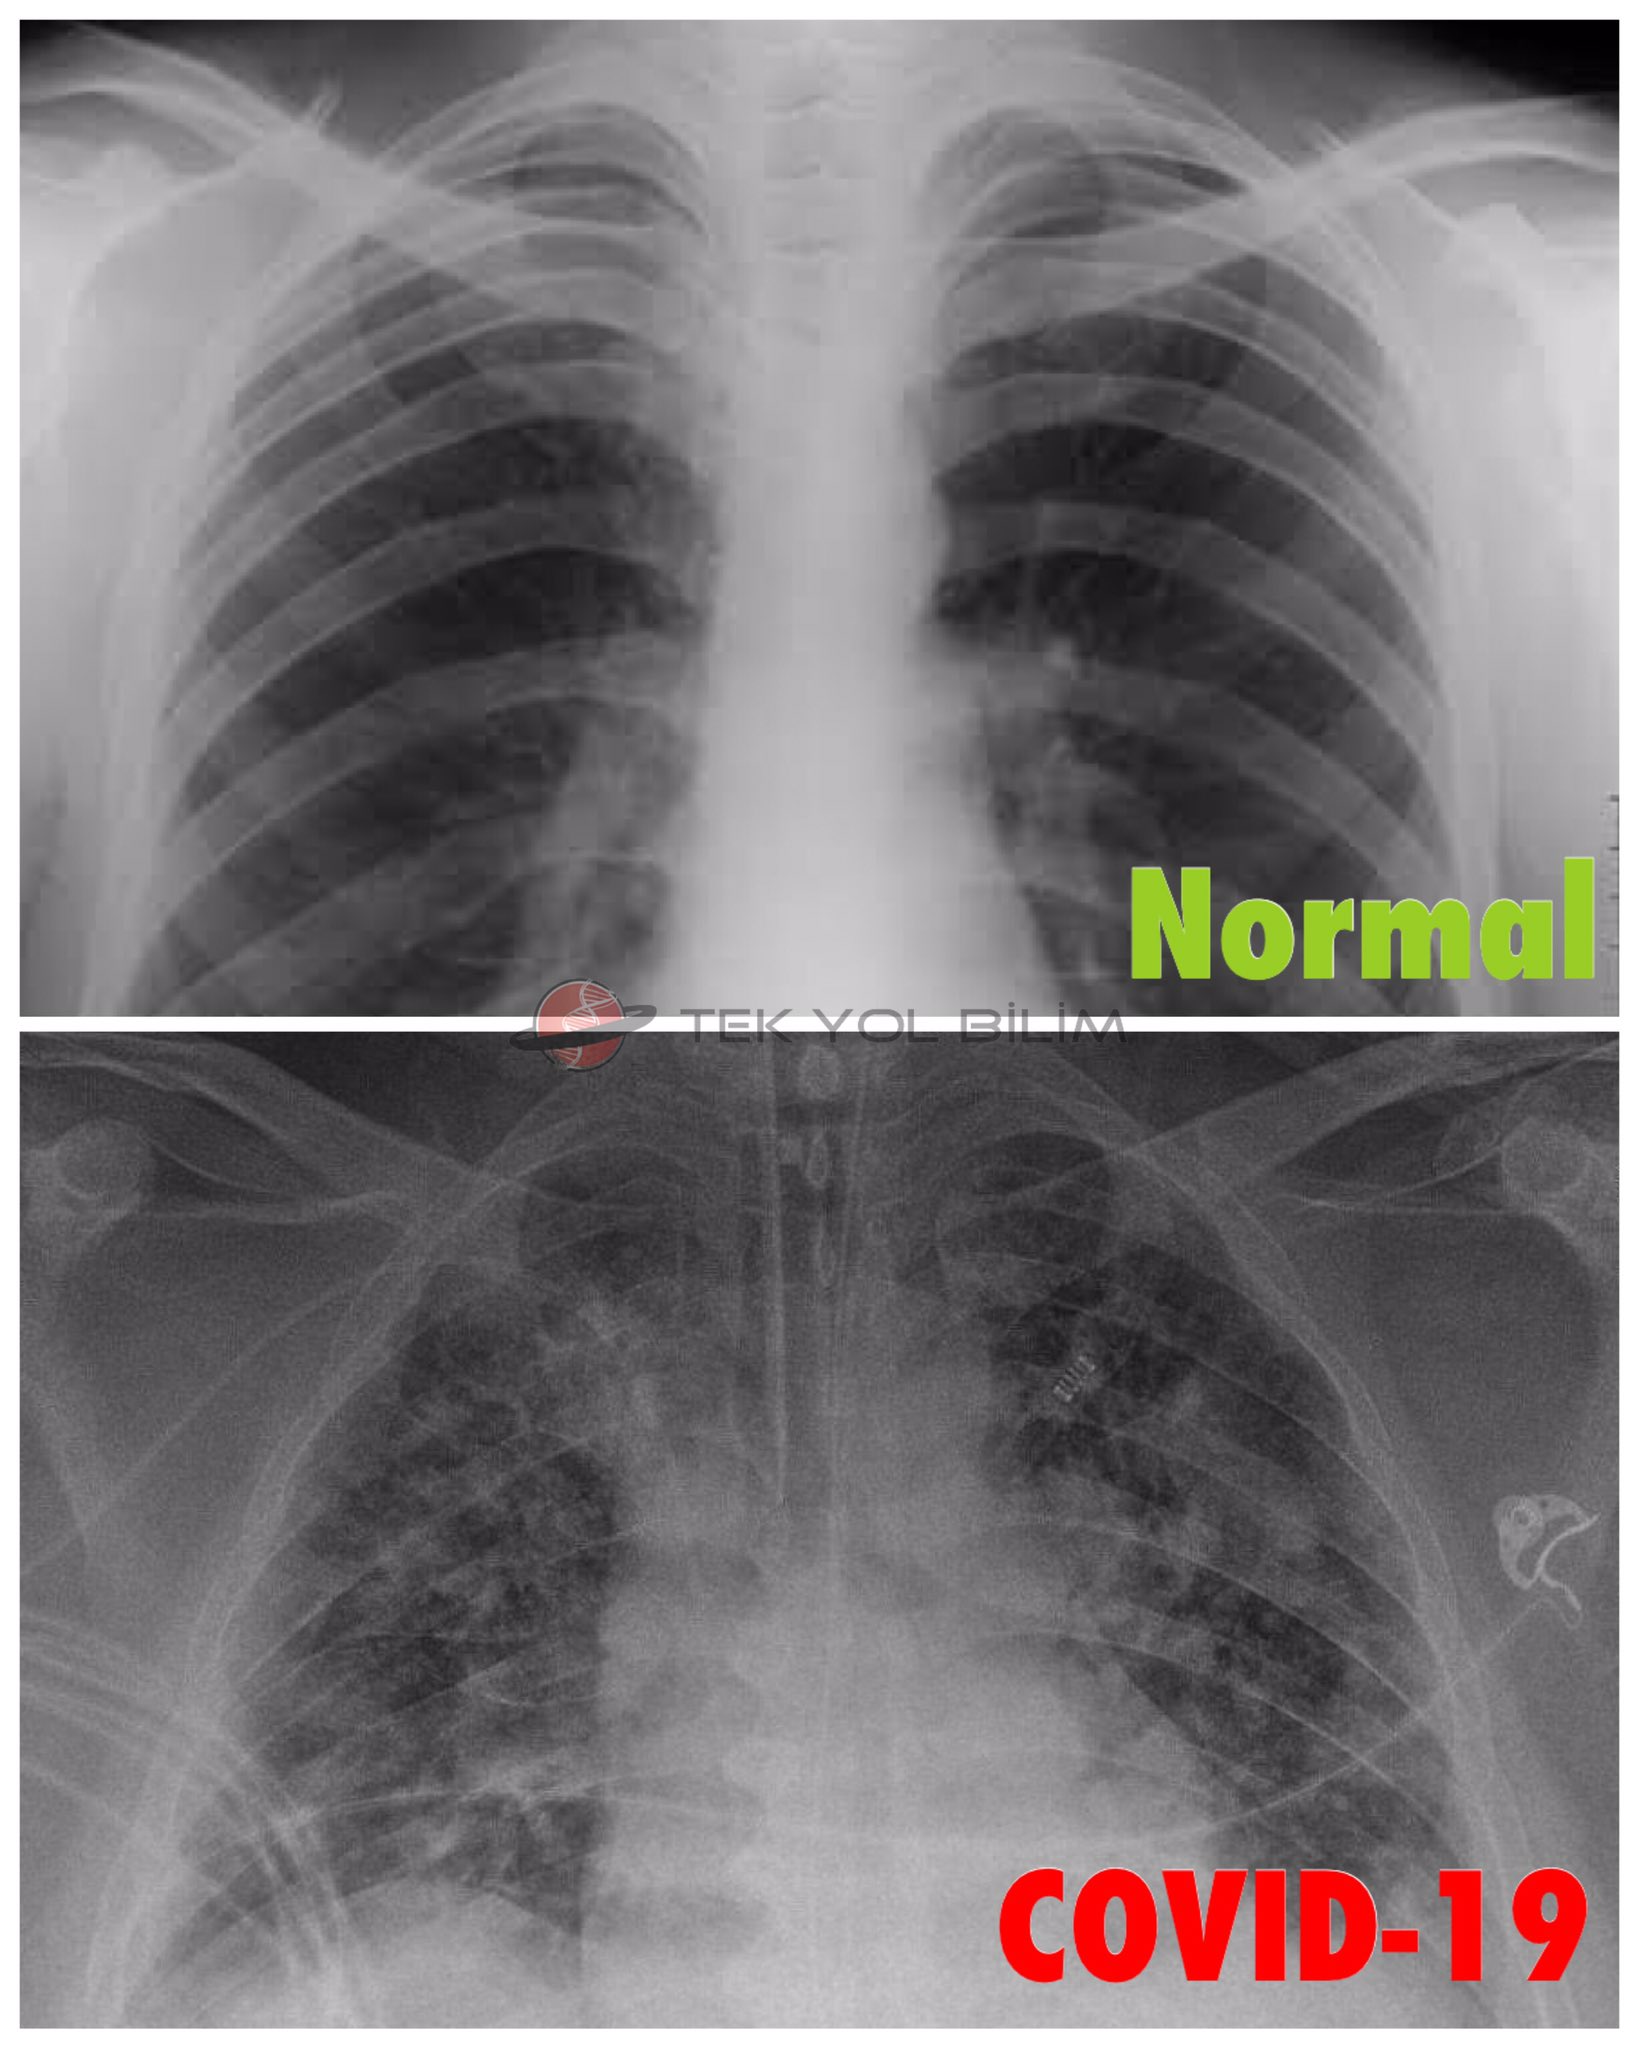

Tek Yol Bilim Platformu On Twitter Saglikli Bir Insanin Akciger Filmi Vs Covid 19 Hastasinin Akciger Filmi Yeni Tip Koronavirus Sarscov2 Akcigerlerin Oksijenlenmesini Engelleyerek Bu Hale Getiriyor Https T Co Suqtmx3i0e